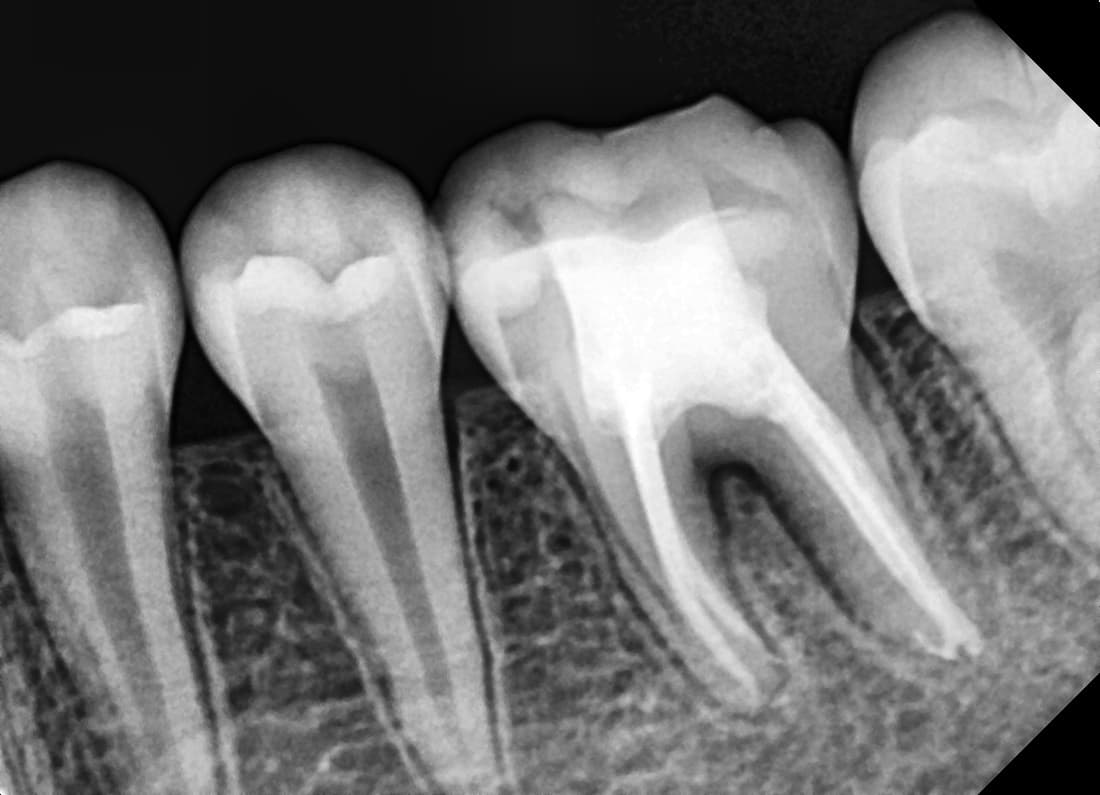

치근단절제술

뿌리 끝까지 염증이 번진 앞니

Before

After

재신경치료 및 치근단절제술 후 병소 완치